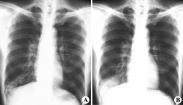

支氣管擴張癥狀

• 支氣管擴張

628健康網為您分享有關支氣管擴張的癥狀,支氣管擴張的治療方法,支氣管擴張的預防知識,支氣管擴張的癥狀圖片,支氣管擴張...